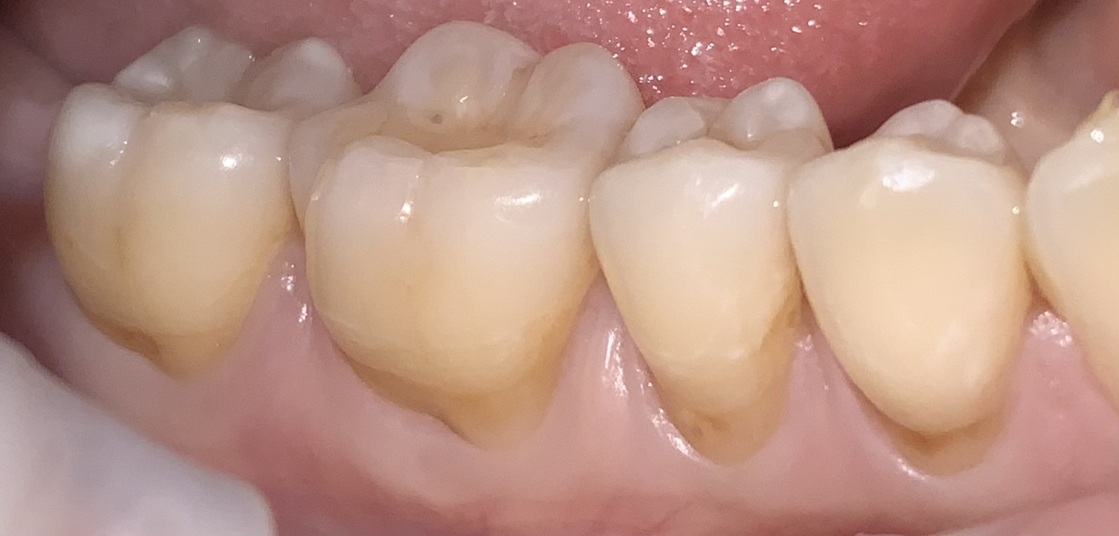

Before & After

Below are examples of the cosmetic outcomes that may be achieved with BPA-free gum coverings. Images are used with full patient consent. Individual results may vary.